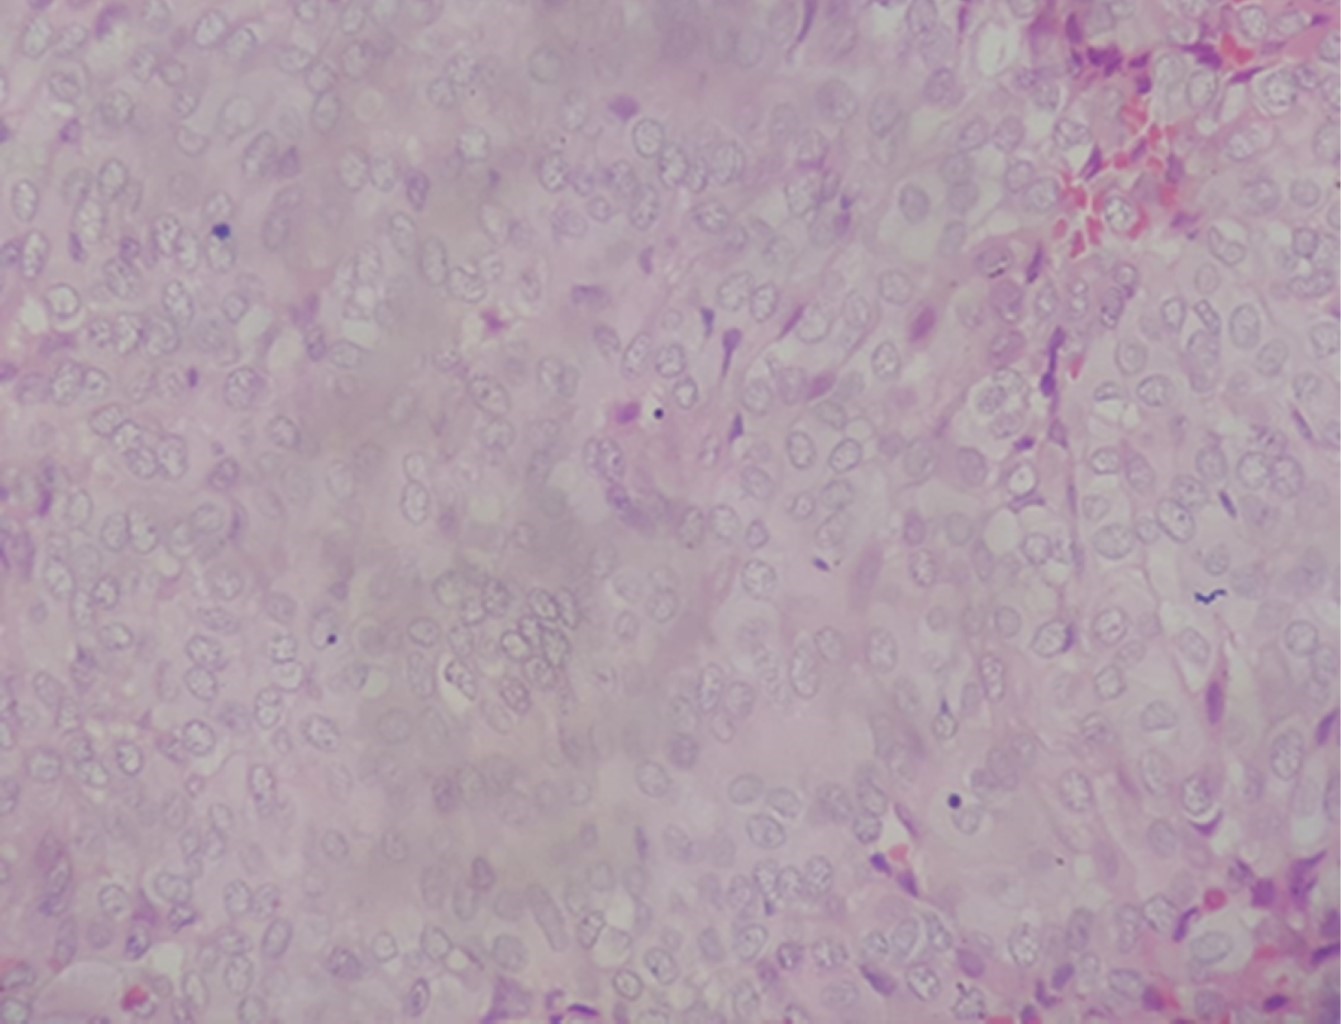

Histopatológicamente, estos tumores muestran una amplia gama de características histológicas, mostrando proliferación neoplásica maligna de células epiteliales de aspecto acinar con presencia de citoplasma basófilo, escasas mitosis dentro de una leve atipia dispuesta en mantos sólidos con permeación linfática y venosa (Figuras 7, 8, 9 y 10).

Figura 7

Figura 8

Figura 9

Figura 10